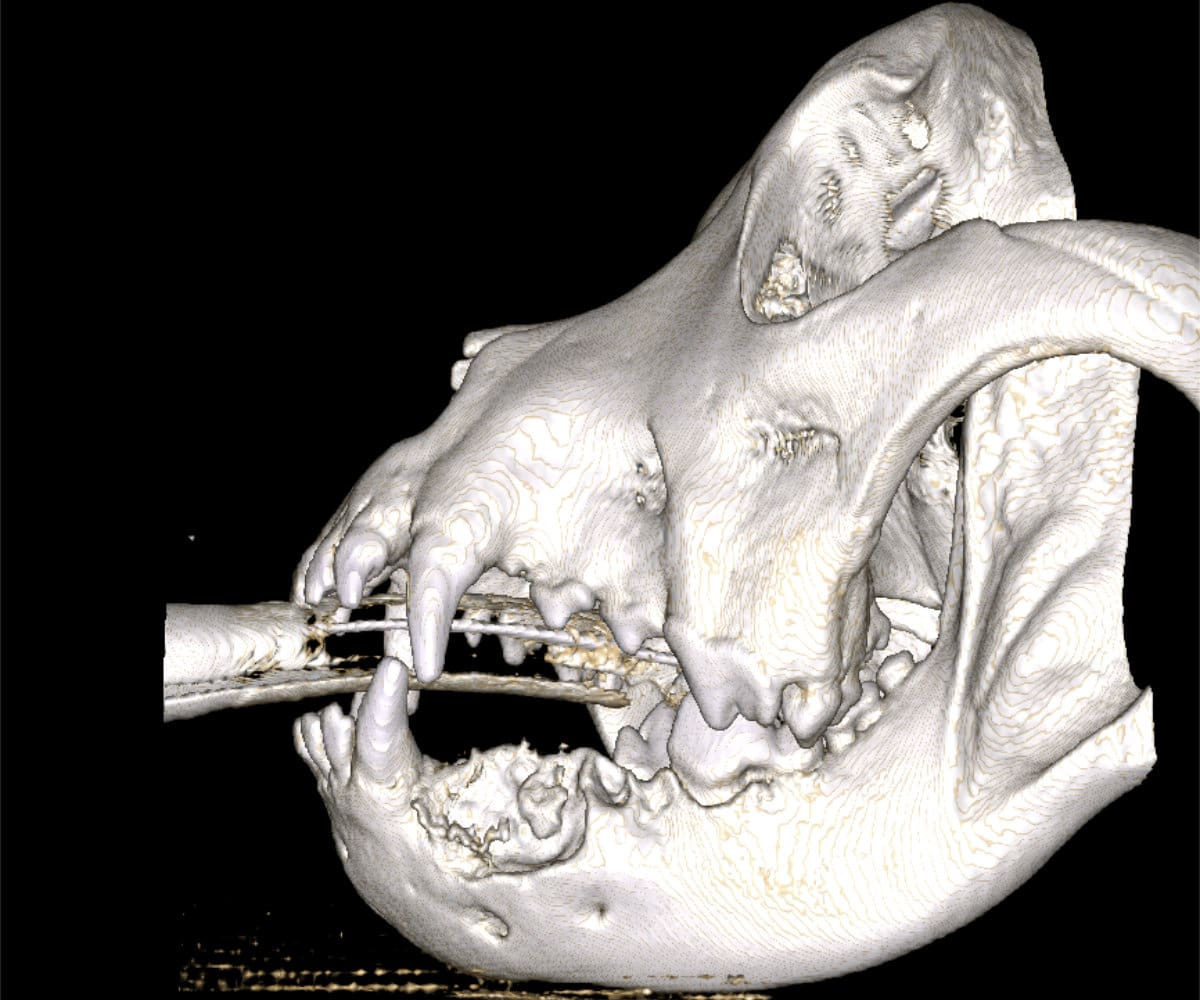

In addressing these limitations, CBCT emerges as a pivotal advancement. Conducting a CBCT scan on our patients is characterized by minimal time and effort, effectively reducing anesthesia duration. Moreover, this technology facilitates the generation of a comprehensive 3D reconstruction of the teeth and skull, surpassing the constraints of traditional radiographs. This innovative approach empowers our veterinary professionals to identify oral pathologies that may have been missed on traditional radiographs.

The advantages extend beyond diagnosis, as CBCT enables intricate 3D reconstructions of the skull, providing invaluable support to our doctors in the meticulous planning process for facial plating procedures.

Cone beam CT technology provides veterinarians with 3-dimensional images in far greater detail than dental radiographs. CBCT scans significantly decrease the amount of time a patient spends under anesthesia compared to the time it takes to complete dental radiographs.

Our CBCT VetCAT unit is easily rolled up to our treatment table and takes only 40 seconds to complete a scan. It has proven to be invaluable in the diagnosis and treatment planning for pets with periodontal, endodontic and cancerous disease conditions. It is also indispensable in the evaluating our trauma cases with jaw fractures.